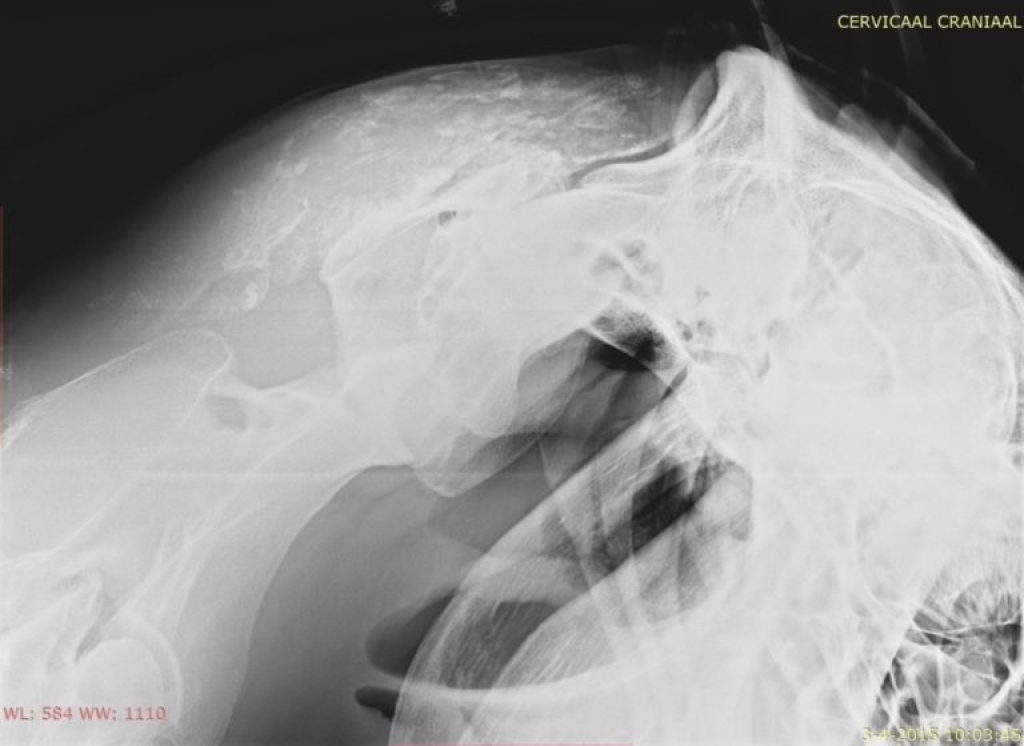

Links: Overvulling en verkalkingen van de slijmbeurs van de nekband

Overvulling en verkalkingen van de slijmbeurs van de nekband